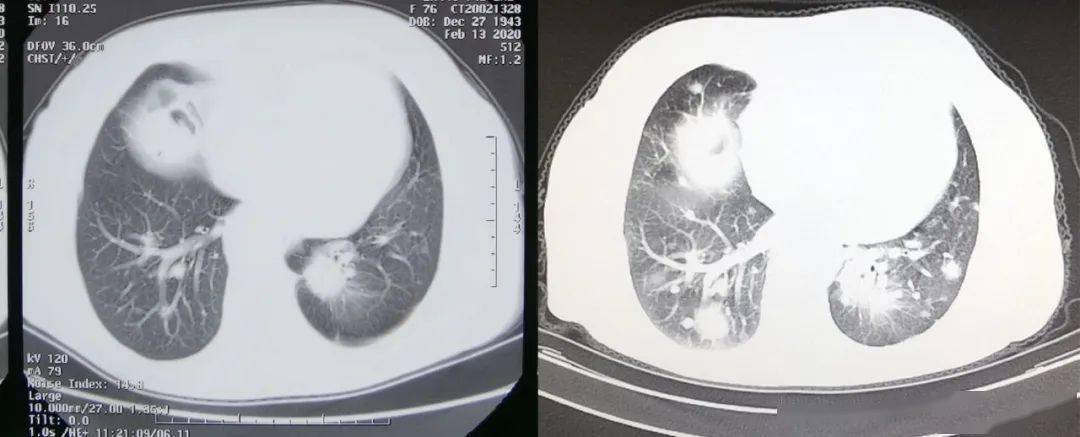

右肺腺癌术后3年肺内转移结节射频消融病例分享

肺癌病例73岁晚期肺腺癌生存期接近4年